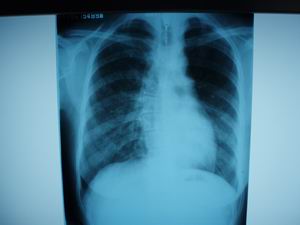

病人36岁,女、5年前就有过一次咳嗽发烧,当时也没诊断清,市级医院说是支气管肺炎,后来消炎加抗痨治疗了4个月就好了。这次病人主要是胸闷,晚上有点低烧3天,咳血痰,请各位老师帮忙看看诊断什么病

图像不清楚,两肺下野参出性病变。

胸椎右弯!图像不清楚,两肺下野参出性病变。

1)右肺感染性病变;建议抗炎治疗后复查,必要时行ct扫描检查。2)脊柱胸段右突侧弯。

右肺感染性病变,脊柱胸段右侧弯曲畸形

右肺条片影,考虑右下肺炎性改变。

右肺感染性病变;建议抗炎治疗后复查,必要时行ct扫描检查。脊柱胸段右突侧弯。

)右肺感染性病变,考虑右肺下野支气管扩张,建议抗炎治疗后复查,必要时行ct扫描检查